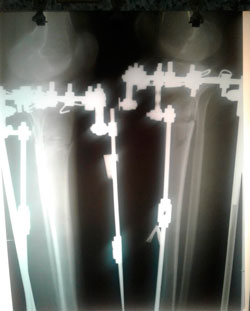

Дата операции - 19.06.2018г.

Дата снятия аппаратов - 15.10.2018г.

Срок лечения - 115 дней.